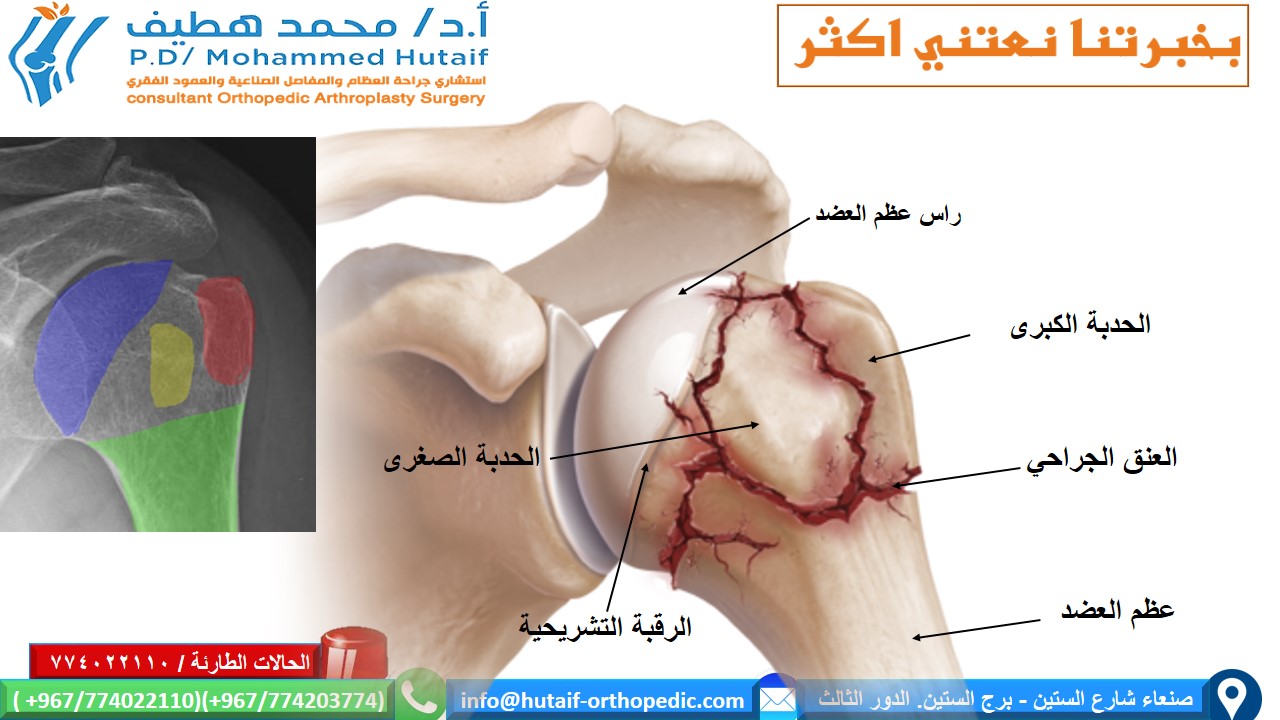

كسور لوح الكتف: تشخيص دقيق، علاج فعال، وتعافٍ أسرع!